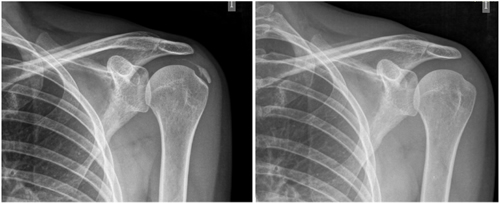

The average number of sessions in our series was 20. The criteria for continuing or stopping treatment was the radiological and clinical evolution (Figures 4 and 5). The interventions were performed up to a maximum of 40 sessions. Perrón treated patients for 9 sessions (3 weekly sessions for 3 weeks) (14). Leduc treated with 10 sessions (3 per week for the first two weeks; then one weekly for 4 weeks) (15). Rioja-Toro treated patients for 40 sessions (5 times per week) and evaluated them at 20 and 40 sessions (3). Chico-Álvarez treated patients between 15 and 30 sessions depending on the radiological evolution (5 times per week) (1).

Fig. 4. 47-year-old female patient with formative right supraspinatus calcific tendinitis who, after 30 sessions of iontophoresis, decreased pain measured by VAS from 6/10 to 3/10 and calcification from 38 mm to 8 mm (assessments at onse and at 10, 20 and 30 sessions, respectively).